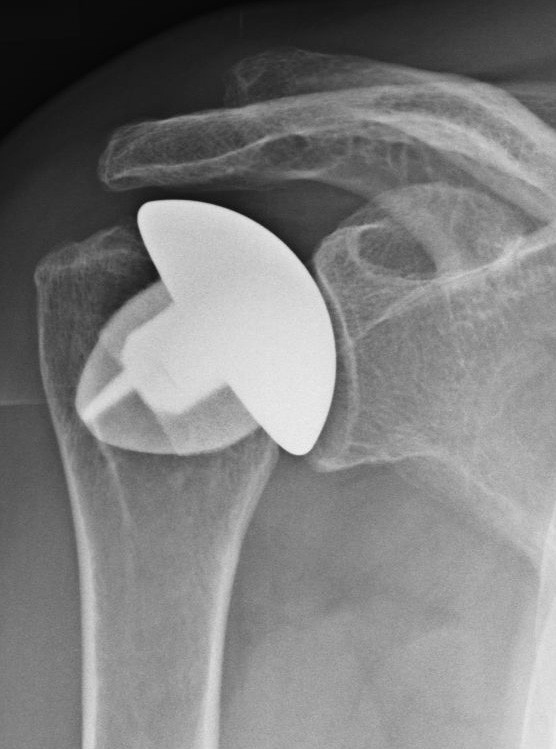

Das Fallbeispiel zeigt ein Röntgenbild mit Arthrose von Kopf und Pfanne mit aufgebrauchtem Gelenkspalt und ein postoperatives Röntgenbild nach 3 Jahren mit eingebrachter TEP (Kopf und Pfanne wurden ersetzt). Da die Gelenkpfanne aus Polyethylen ist, kann man sie auf dem Röntgenbild nicht so genau sehen wie die Kopfprothese.